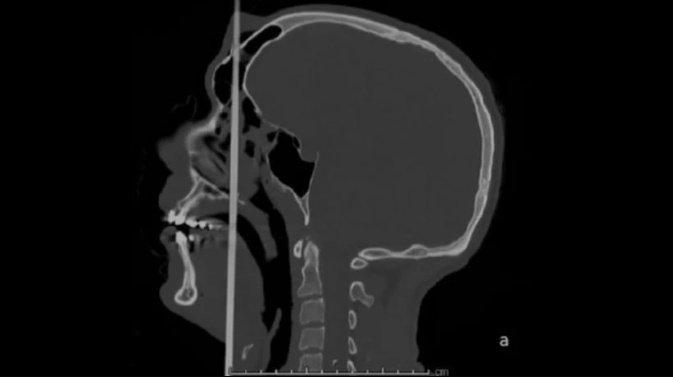

Стрела вошла в голову в районе подбородка и вышла посреди лба. Когда на место происшествия прибыла бригада медиков, француз был в сознании, кровотечения у него не было. Рот открыть пациент не мог, так как стрела прошла сквозь ротовую полость и спровоцировала сильный спазм.

3D-модель полученной травмы. Фото © Le Monde